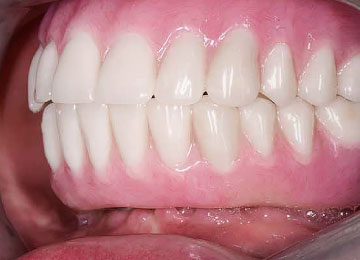

Имплантация зубов: фото "До" и "После"

Фото ДО

Фото ПОСЛЕ

Наведите для просмотра

All-on-4